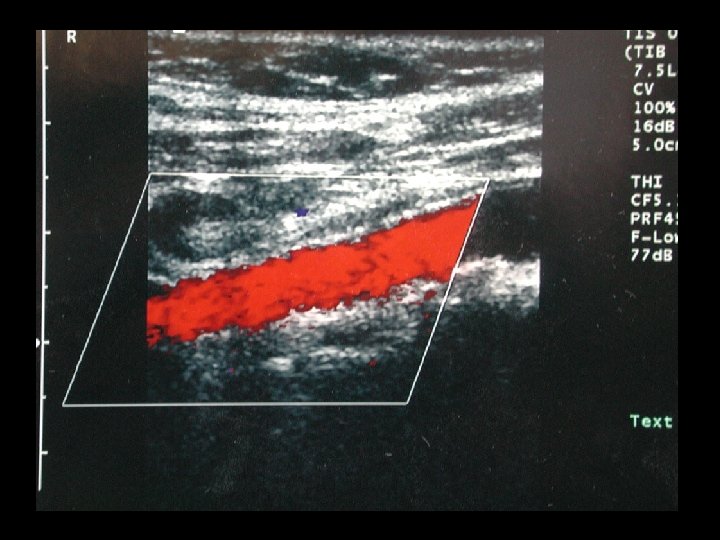

GİRİŞİMSEL RADYOLOJİDE KULLANILAN RADYOLOJİK YÖNTEMLER üFloroskopi üDSA (digital substraction angiography) üUSG üRenkli Doppler USG üBT üMR